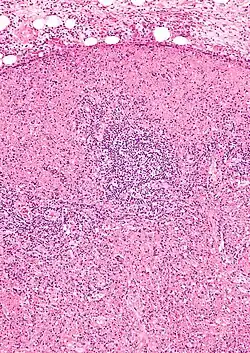

Micrograph of a lymph node with Kikuchi disease showing the characteristic features (abundant histiocytes, necrosis without neutrophils). H&E stain.